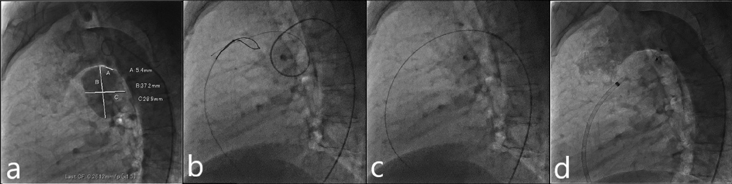

入院翌日に経皮的動脈管閉鎖術を施行した.局所麻酔後,右大腿静脈に6 Fr 11 cm sheath(Medikit Inc., Tokyo),右大腿動脈に5 Fr 11 cm sheath(Medikit Inc., Tokyo)を留置した.カテーテル検査の結果Qp/Qsは1.05,肺血管抵抗係数は0.57 Wood unit·m2.大動脈造影でDAAが造影され,瘤入口部径は5.4 mm,瘤最大径は28.9×37.2 mm,瘤流出部径は2.2 mmであった(Fig. 3a).5 Frジャドキンス型右冠動脈用(JR)カテーテル(Hanaco Medical, Saitama, Japan)を逆行性に進めて瘤入口部にかけて,そこから0.035̋Radifocus guidewire 260 cm(Terumo Inc., Tokyo)を瘤内へ進めて,1ループさせて主肺動脈まで進めた.続いて,順行性に進めて主肺動脈に留置した6 Fr wedge pressure catheter(Gadelius Medical, Kanagawa, Japan)から15 mm径の6 Fr Amplatz goose neck snare (Medtronic plc., Ireland)を進めて,Radifocus guidewire先端を把持して(Fig. 3b)右大腿静脈のsheath外まで引き出した.瘤内のループを伸ばして,大腿静脈–DAA–大腿動脈のwire loopを作成した(Fig. 3c).DAAの大動脈側入口部径が5.4 mmであったため,ADO 12 mm/10 mm(Abbott Structural Heart, Plymouth, MN, USA)を同部に留置した:右大腿静脈のsheathを抜去し,7 Fr Amplatzer™ TorqVue 180 (Abott, Pylmouth, MN, USA)を下行大動脈まで進めた.ADOのRetention skirtを展開して瘤入口部にかけて,デバイスボディを瘤内に展開した.留置後の大動脈造影では閉鎖栓突出による大動脈の狭窄はなく,遺残短絡はごく少量であった(Fig. 3d).特に合併症は認めず,治療翌日からアスピリン100 mgの内服を開始し,退院した.治療後の経過は良好で,術後1カ月の心臓超音波検査で遺残短絡は消失し,術後3カ月の胸部造影CT像で瘤内はほぼ血栓化していた(Fig. 4).

Fig. 3 Percutaneous closure of a DAA

a: DAA size: Ao side, 5.6 mm; PA side, 2.2 mm; and maximum diameter, 37.2×28.9 mm. b: The distal end of the Radifocus guidewire is snared in the MPA. c: The Radifocus guidewire is withdrawn into the 6 Fr right femoral sheath to form a wire loop. d: After device deployment, aortic angiography shows no residual leakage from the DAA. DAA, ductus arteriosus aneurysm; MPA, main pulmonary artery.

Fig. 4 Contrast-enhanced chest computed tomography revealing that the DAA is almost thrombosed (black arrow)

DAA, ductus arteriosus aneurysm.